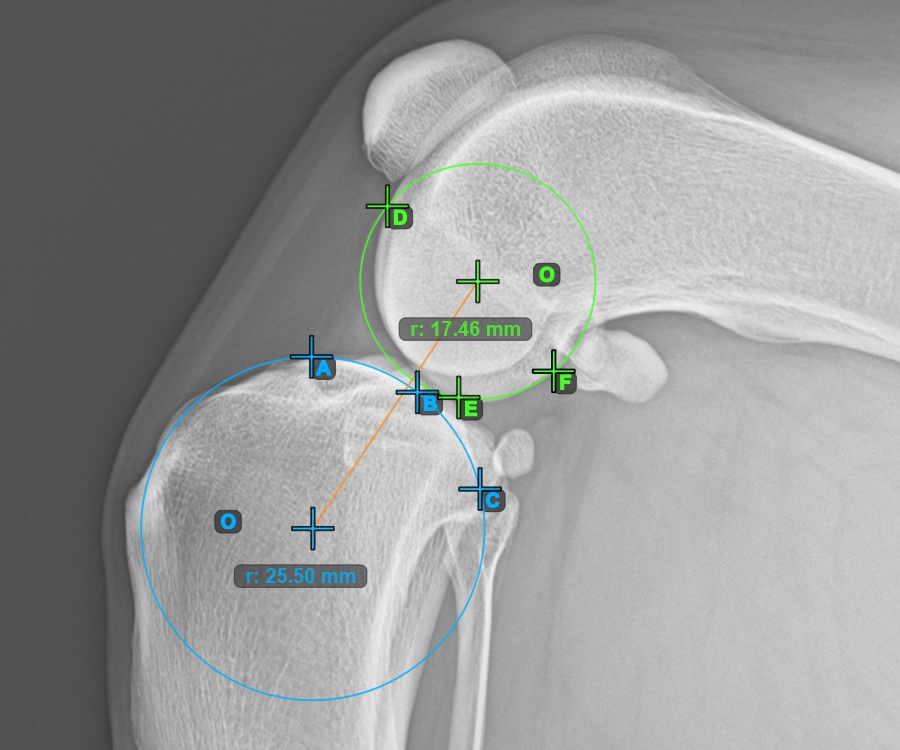

Mark one point in front of the joint on the common tangent between the two circles. A line will be drawn automatically through the marked point.

The image below represents a typical placement of the point on the common tangent between the two circles.